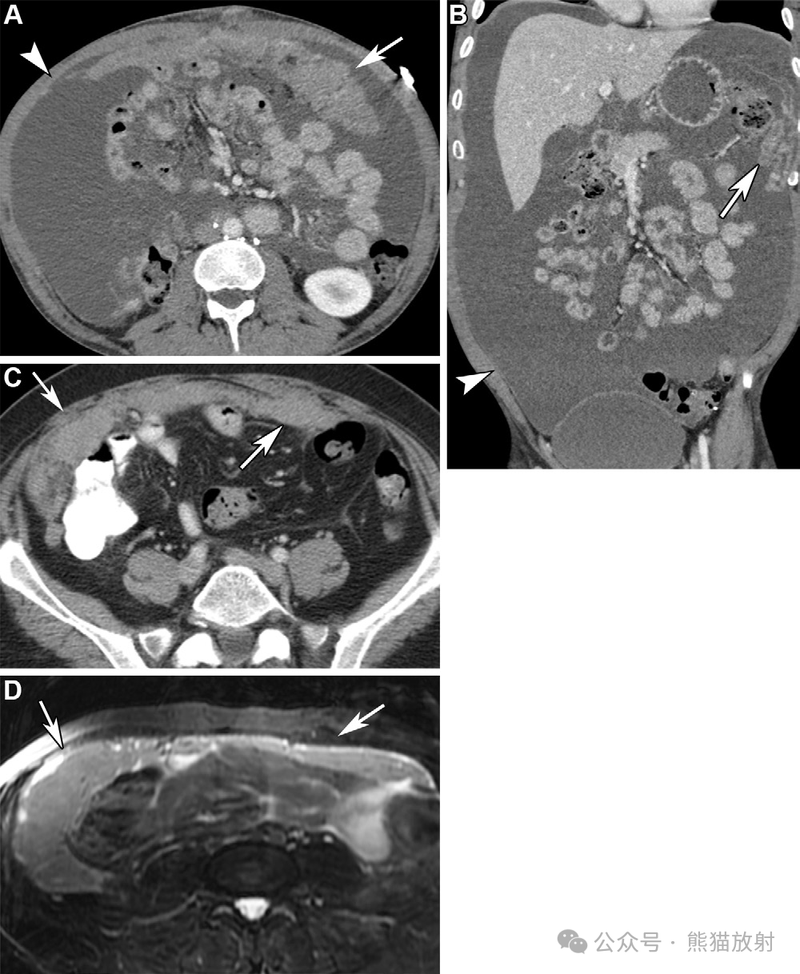

不同类型腹膜间皮瘤两例。(A,B) 46岁男性,湿型上皮样腹膜间皮瘤。腹盆部轴位(A)和冠状 (B) 对比增强 CT 图像显示腹膜不规则增厚,网膜饼形成 (箭)和严重腹水(箭头)。(C,D) 56岁女性,干型上皮样腹膜间皮瘤。腹部轴位增强 CT (C) 和T2WI (D) 图像显示大网膜明显饼状增厚 (箭)。

66岁男性,腹膜间皮瘤,主要累及小肠系膜。腹盆部的轴位 (A) 和冠状 (B) 对比增强 CT 图像显示腹膜结节状增厚(箭)伴小肠系膜片状软组织增厚(箭头),肠系膜呈星芒状表现。